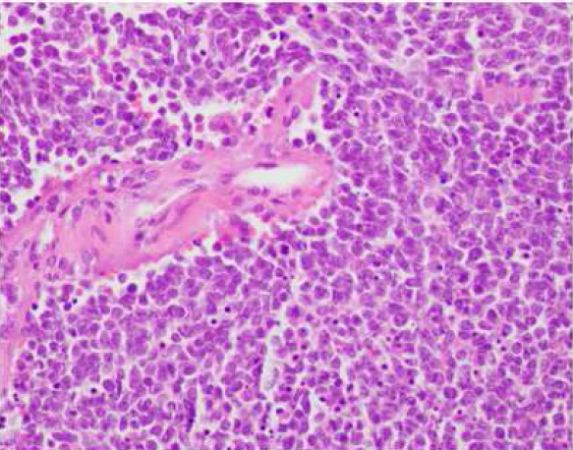

图5. 组织病理切片提示,肿瘤内均匀分布的圆形细胞,核仁明显,细胞质透明空泡化。